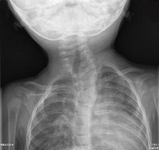

Torcicolo congênito

Radiografia da coluna cervical mostrando inúmeras anomalias de segmentação associadas a uma escoliose convexa cervicotorácica esquerda. Esse paciente apresentou-se com inclinação da cabeça. Há anomalias de segmentação na região torácica inferior e cervical superior. Há uma escoliose convexa cervicotorácica esquerda aguda com uma hemivértebra no ápice da curva. Vértebra em borboleta identificada no sentido rostral à hemivértebra e as anomalias de segmentação também são identificadas no sentido caudal à hemivértebra

Do acervo pessoal da Dra. Joyce L. Oleszek; usado com permissão